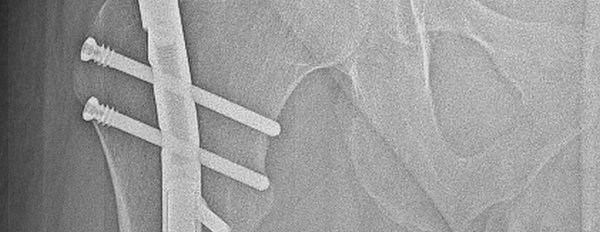

Last month, such an innovative operation was performed at Rehasport Hospital by Bartosz Musielak, MD, performing a lower limb lengthening procedure with distraction osteotomy and PRECICE magnetic nail implantation. The lower limb lengthening procedure consisted of placing a NuVasive PRECICE growing magnetic nail inside the marrow canal of the bone with a minimally invasive, percutaneous bone cut. This unique telescopic rod is equipped with a special mechanism activated by an external controller responsible for its gradual elongation.